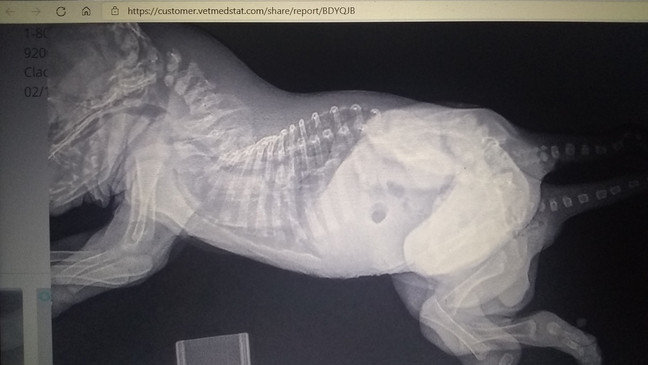

She has a type of congenital conjoining disorders called monocephalus dipygus and monocephalus rachipagus dibrachius tetrapus; which simply means she has one head and chest cavity, but two pelvic regions, two lower urinary tracts, two reproductive systems, two tails and six legs among other things according to Neel veterinarians.

Skipper's human family says she has been doing great at home and is beginning to crawl around but her outside legs are dominant and inside legs are recessive.